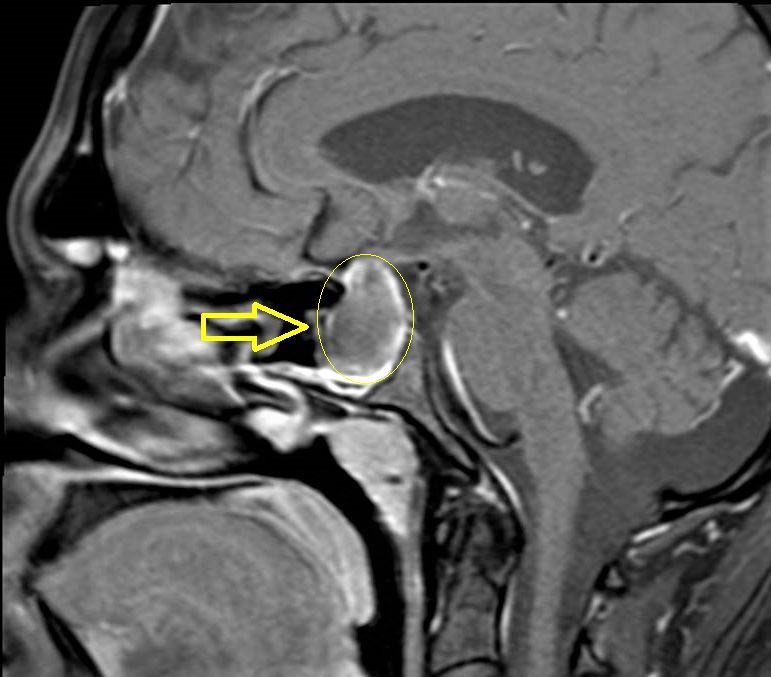

وتمكّن الفريق الطبي المكون من جراحة المخ والأعصاب والعمود الفقري بالتعاون مع قسم جراحة الأنف والأذن والحنجرة، من استئصال ورم حميد في قاع الجمجمة لمريض في العقد الثالث من العمر، وذلك عن طريق الأنف بمساعدة منظار جراحي لا يتعدى قطره (3) مليمتر، والوصول إلى الغدة النخامية واستئصال الورم بدون شق جراحي خارجي.